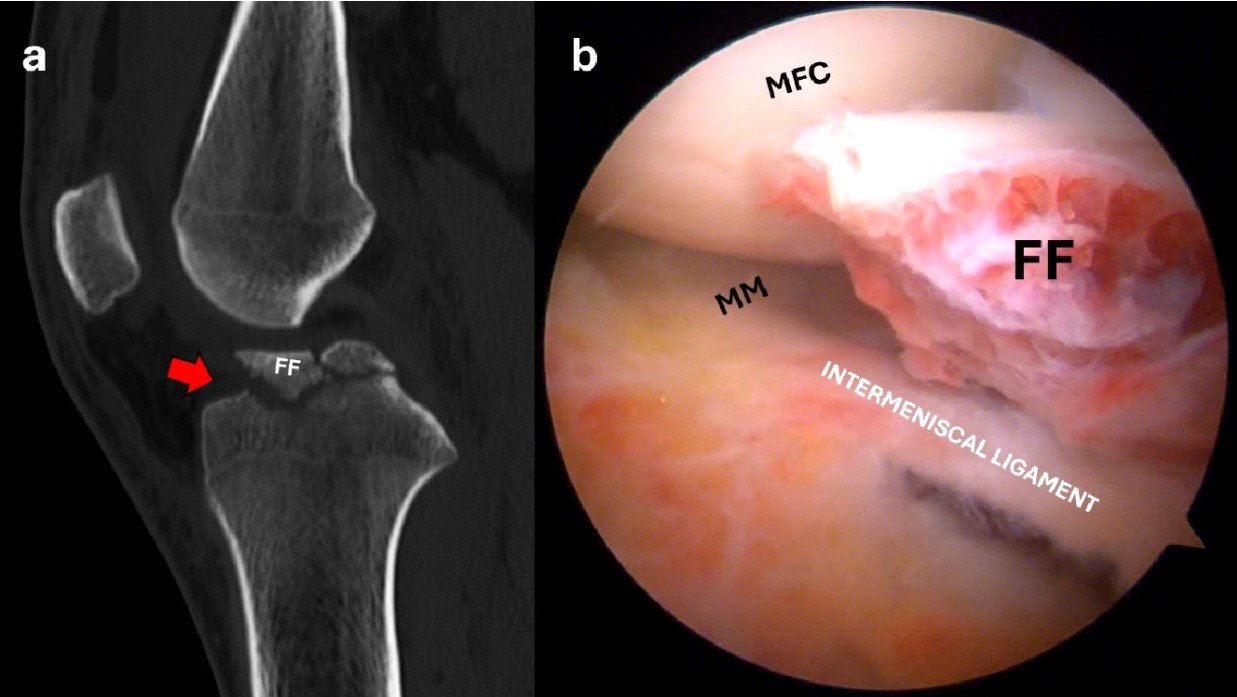

Conventional X-rays are often used as the initial diagnostic tool to identify fractures. CT scan is generally used in ambiguous cases and to better determine the degree of displacement4 (Figure 1). Based on that, the fracture can be classified according to the Meyers and McKeever’s classification in: Type I: minimally/nondisplaced fragment (< 3 mm); Type II: anterior elevation of the fragment; Type III: complete separation of the fragment (Type IIIa involves a small portion of the eminence; Type IIIb involves the majority of the eminence); Type 4: comminuted avulsion or rotation of the fracture fragment5. Alternatively, Green et al6 highlight the key role of MRI in the assessment of tibial eminence fracture because of the possibility to identify associated injuries such as meniscal tears (Figure 2) or ligamentous damage6,7. In our experience, additional soft tissue injuries such as meniscal entrapment or ACL injuries are identified alongside the fracture in a substantial number of cases8-10. The treatment approach depends on the severity of the fracture, with nondisplaced fractures often treated conservatively with immobilization in extension for 4-6 weeks11. However, in cases where there is a significant displacement, surgical intervention is typically required to prevent long-term instability, nonunion, or malunion12. Different surgical approaches have been proposed to manage tibial avulsion fractures. Among them, Arthroscopic Reduction and Internal Fixation (ARIF) has gained increasing preference over open techniques due to its minimally invasive nature, fast recovery times, and limited complications.

Figure 1. Sagittal CT scan showing a displaced anterior eminence fracture (red arrow) (a); the arthroscopic view shows the interposition of the intermeniscal ligament and the fracture bed (b). FF, fracture fragment; MM, medial meniscus; MFC, medial femoral condyle.